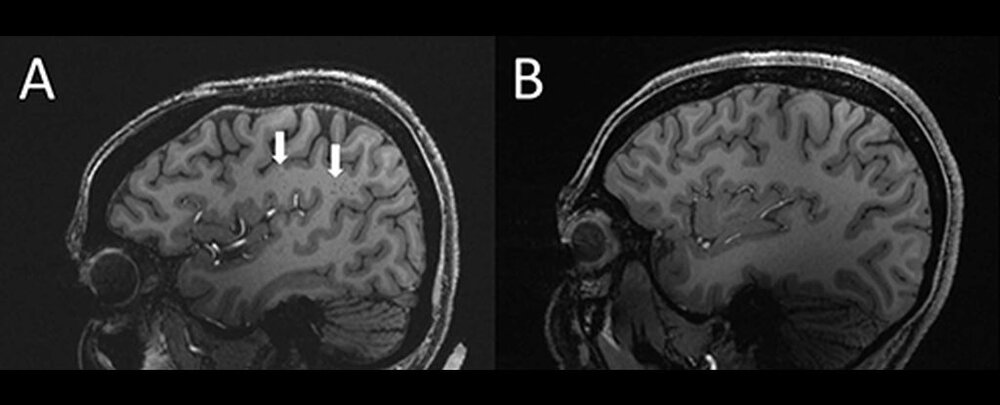

نگارعلی_ با استفاده از MRI با وضوح فوق العاده بالا، محققان دریافتند که فضاهای اطراف عروقی - فضاهای پر از مایع در اطراف رگ های خونی مغز - در بیمارانی که هم میگرن مزمن و هم اپیزودیک را تجربه می کنند، به طور غیرعادی بزرگ می شود.

دانشمند پزشکی ویلسون ژو از دانشگاه کالیفرنیای جنوبی در لس آنجلس می گوید: در افراد مبتلا به میگرن مزمن و میگرن اپیزودیکه، تغییرات قابل توجهی در فضاهای اطراف عروقی ناحیه ای از مغز به نام centrum semiovale وجود دارد.

زو و همکارانش در مورد فضاهای دور عروقی در مرکز نیمه اوال، ناحیه مرکزی ماده سفید مغز دقیقا زیر قشر مغز کنجکاو بودند. عملکرد این فضاها به طور کامل درک نشده است. آنها در تخلیه حرکت سیال نقش دارند و بزرگ شدن آنها می تواند نشانه ای از یک مشکل بزرگتر باشد.

اسکن ها نشان داد که فضاهای اطراف عروق در مرکز نیمه اوال بیماران مبتلا به میگرن در مقایسه با گروه کنترل به طور قابل توجهی بزرگ شده است.

اگرچه ماهیت ارتباط بین فضاهای اطراف عروقی بزرگ و میگرن نامشخص است، نتایج نشان میدهد که میگرن با مشکلی در لولهکشی مغز همراه است، سیستم گلیمفاتیکی که مسئول پاکسازی مواد زائد در مغز و سیستم عصبی است. از کانال های اطراف عروقی برای حمل و نقل استفاده می کند.